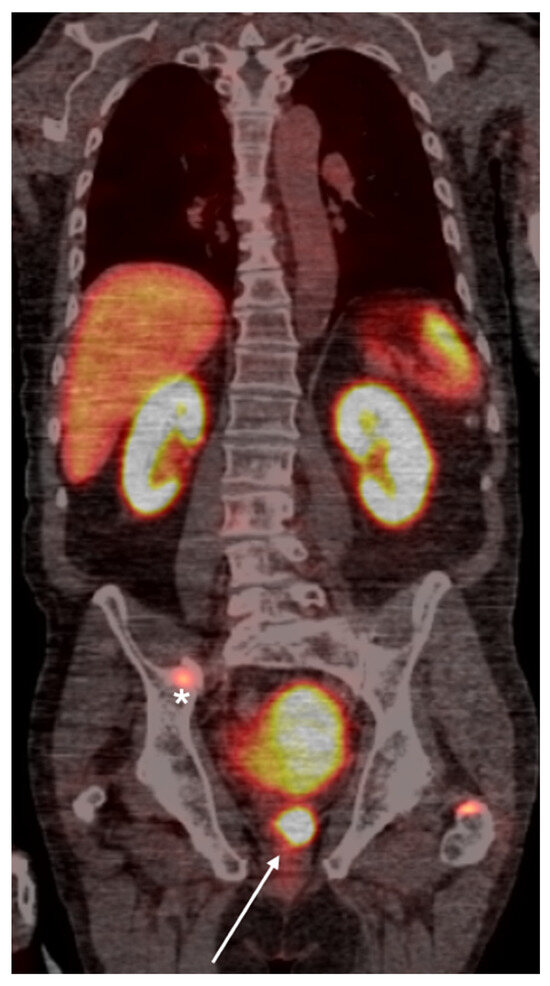

4. PSMA PET Imaging

- Adnan, A.; Basu, S. PSMA Receptor-Based PET-CT: The Basics and Current Status in Clinical and Research Applications. Diagnostics 2023, 13, 158. [Google Scholar] [CrossRef]

- Roberts, M.J.; Maurer, T.; Perera, M.; Eiber, M.; Hope, T.A.; Ost, P.; Siva, S.; Hofman, M.S.; Murphy, D.G.; Emmett, L.; et al. Using PSMA imaging for prognostication in localized and advanced prostate cancer. Nat. Rev. Urol. 2023, 20, 23–47. [Google Scholar] [CrossRef]

- Jochumsen, M.R.; Bouchelouche, K. PSMA PET/CT imaging in prostate cancer: Impact on clinical management and patient outcomes. Clin. Nucl. Med. 2024, 49, 1–10. [Google Scholar]

- Houshmand, S.; Salavati, A.; Solnes, L.B. Clinical applications of PSMA PET in prostate cancer management. PET Clin. 2023, 18, 1–18. [Google Scholar]

- Fendler, W.P.; Calais, J.; Eiber, M.; Flavell, R.R.; Rettig, M.B. PSMA PET for prostate cancer imaging: The current status and future directions. J. Nucl. Med. 2023, 64, 28–37. [Google Scholar]

- Fanti, S.; Goffin, K.; Hadaschik, B.A.; Herrmann, K.; Maurer, T.; MacLennan, S.; Oprea-Lager, D.E.; Oyen, W.J.; Rouvière, O.; Mottet, N.; et al. Consensus statements on PSMA PET/CT response assessment criteria in prostate cancer. Eur. J. Nucl. Med. Mol. Imaging 2021, 48, 469–476. [Google Scholar] [CrossRef]

- Shagera, Q.A.; Karfis, I.; Kristanto, P.; Spyridon, S.; Diamand, R.; Santapau, A.; Peltier, A.; Roumeguère, T.; Flamen, P.; Artigas, C. PSMA PET/CT for Response Assessment and Overall Survival Prediction in Patients with Metastatic Castration-Resistant Prostate Cancer Treated with Androgen Receptor Pathway Inhibitors. J. Nucl. Med. 2023, 64, 1869–1875. [Google Scholar] [CrossRef]